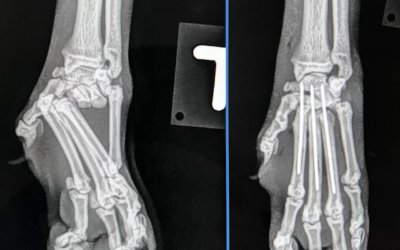

Kreuzbandriss beim Hund

Der Kreuzbandriss beim Hund ist die häufigste Ursache für einen Besuch beim Orthopäden. Eine frühe Diagnose und chirurgische Versorgung sind entscheidend für die langfristige Lebensqualität.